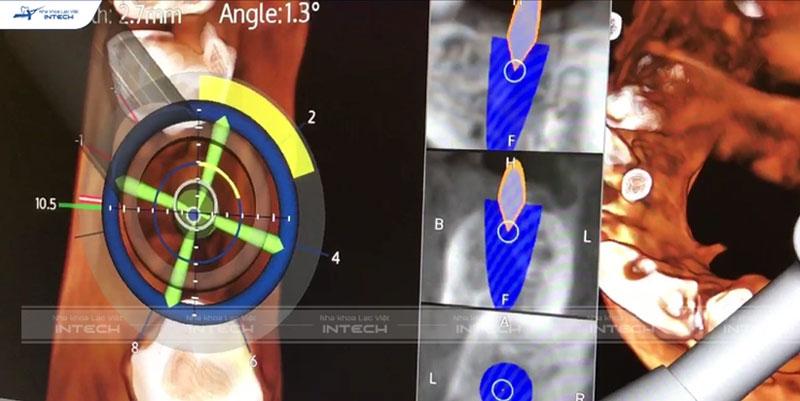

Trồng răng Implant bằng Robot định vị X-Guide

Robot định vị là công cụ hỗ trợ đắc lực của bác sĩ trong việc hạn chế sai sót và tối ưu hóa kết quả điều trị. Trình độ của bác sĩ là một trong những điều kiện tất yếu trong 1 ca cấy ghép Implant, nhưng nếu trình độ chuyên môn kết hợp với công nghệ Robot định bị sẽ mang lại kết quả chính xác tuyệt đối, gia tăng tỉ lệ thành công.

Tại Nha khoa Lạc Việt Intech kết hợp lên phác đồ điều trị bằng công nghệ Safe Tech và cấy ghép Implant bằng Robot định vị. Nhờ đó cho kết quả chính xác tuyệt đối, an toàn và nhanh chóng gấp 11 lần so với phương pháp truyền thống.

• Hệ thống cảm biến có khả năng điều chỉnh trục và mũi khoan theo đúng hướng.

• Hệ thống camera và GPS mũi khoan trong quá trình phẫu thuật hiển thị trực tiếp trên màn hình cho bác sĩ theo dõi.

• Hệ thống cảm biến chiều sâu của mũi khoan và thông báo bằng âm thanh.

• Không sưng đau, hạn chế chảy máu, tỉ lệ thành công tới 99,8%.

• Hạn chế xâm lấn hay tổn thương các tế bào mô, thúc đẩy quá trình lành thương nhanh.